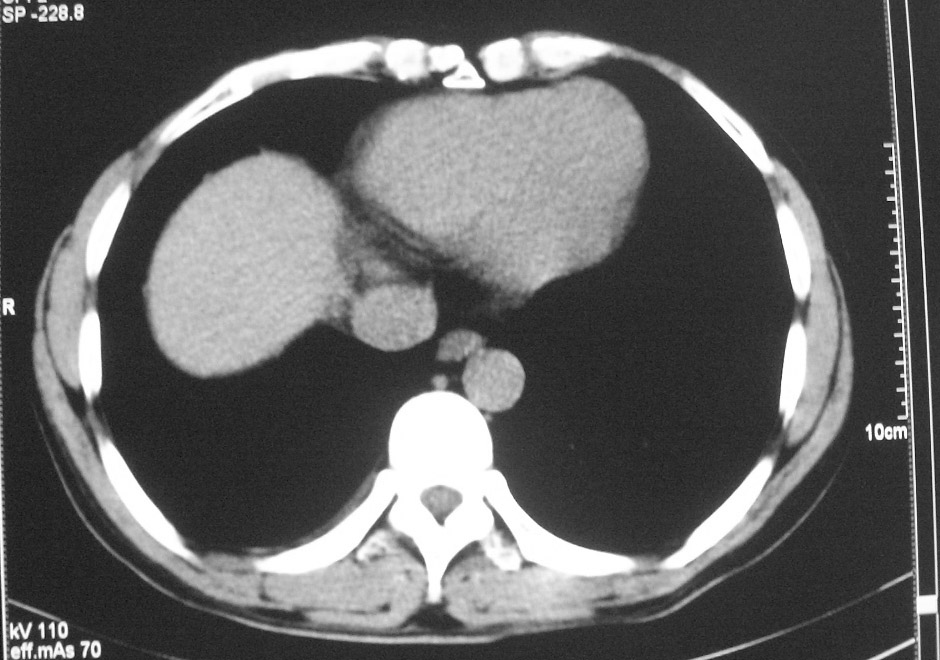

标题: CT5485:[原创]肺部占位请讨论

右肺上叶中央型肺癌并上叶肺不张、纵隔淋巴结肿大

右上叶支气管后壁明显增厚,支持右肺上叶中央型肺癌伴右上叶肺不张、纵隔淋巴结肿大。

右上叶支气管肺癌并右上叶阻塞性不张,右侧少量胸腔积液.

右上叶支气管开口变窄,纵隔见肿大的淋巴结。支持右上叶中心型肺癌并右上叶不张纵隔淋巴结肿大。

右肺上叶中央型肺癌并上叶肺不张、纵隔淋巴结肿大.右侧少量胸腔积液。

右上肺中心型肺癌并肺不张,纵膈淋巴结肿大。右侧少量胸腔积液。

右肺上叶支气管后壁增厚,呈鼠尾状狭窄,纵隔内未见明显增大的淋巴结影,考虑为中央型肺癌伴右上肺不张